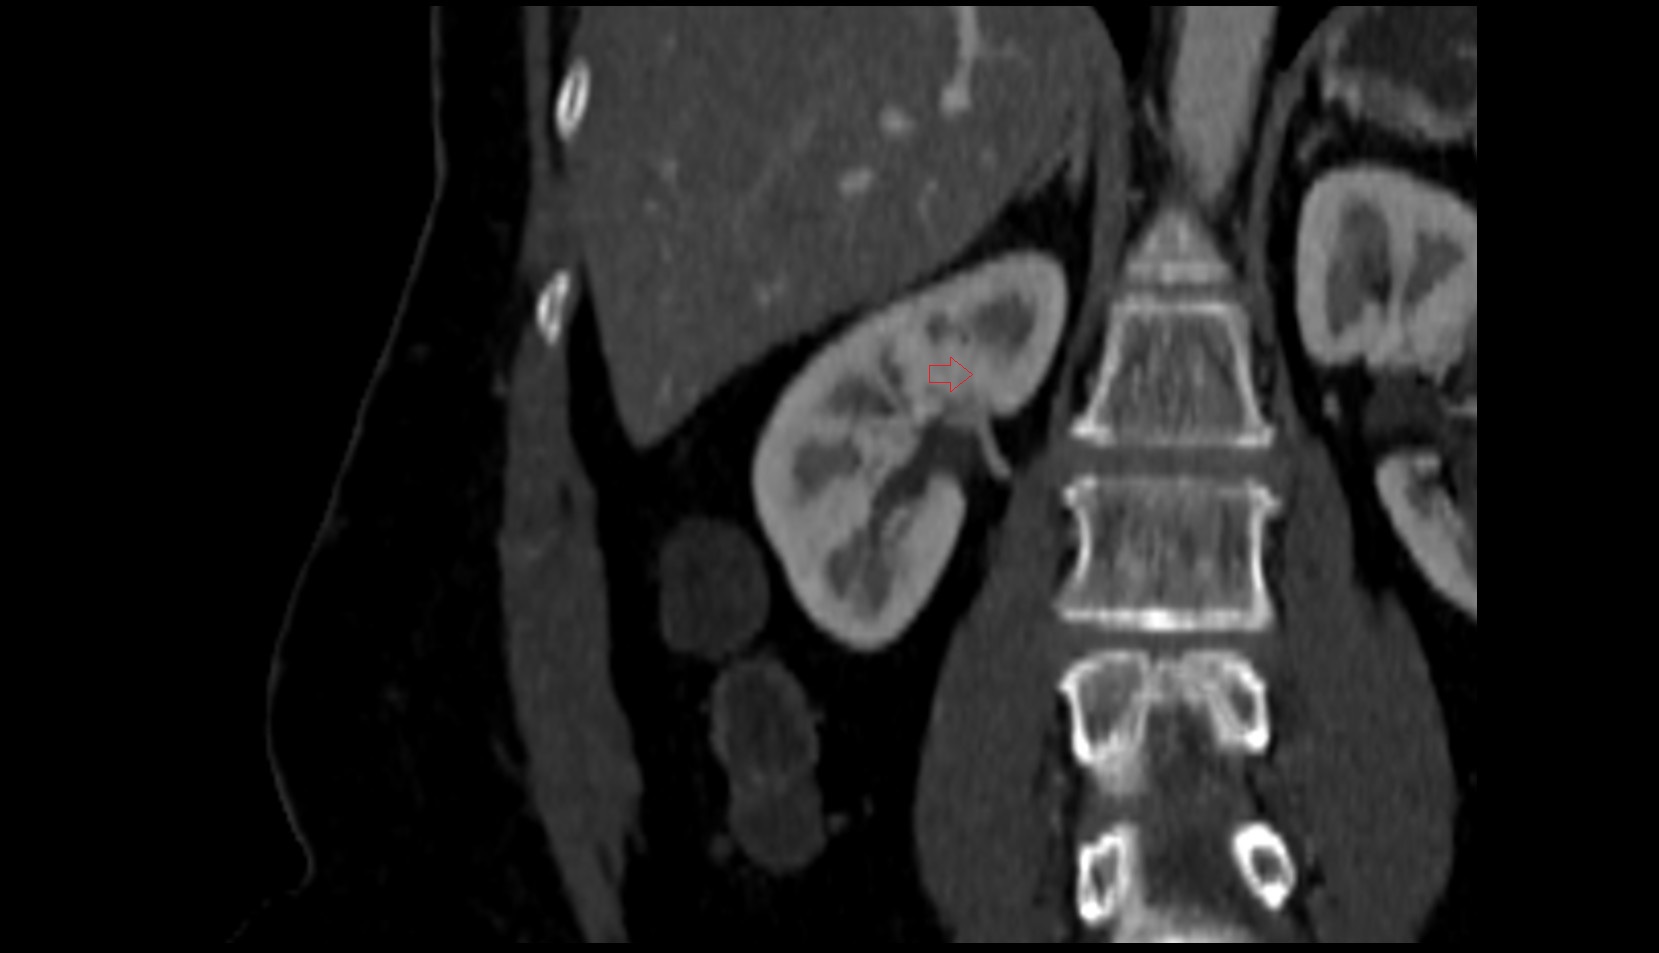

- kidneys

- Right kidney

- Left kidney

- Kidney cortex (Renal cortex)

- Renal capsule

- Renal medulla

- Renal pyramids

- Renal artery

- Renal vein